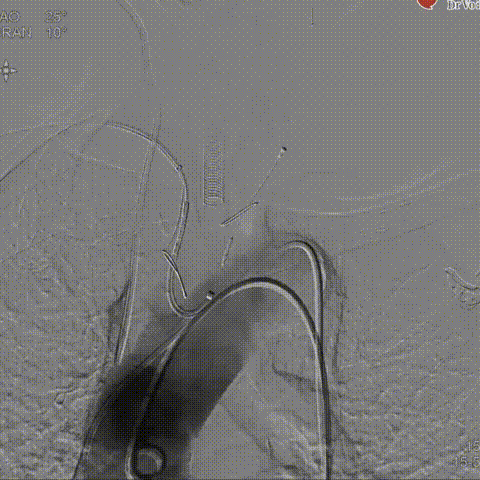

术后造影

瓣膜释放后造影

球囊后扩